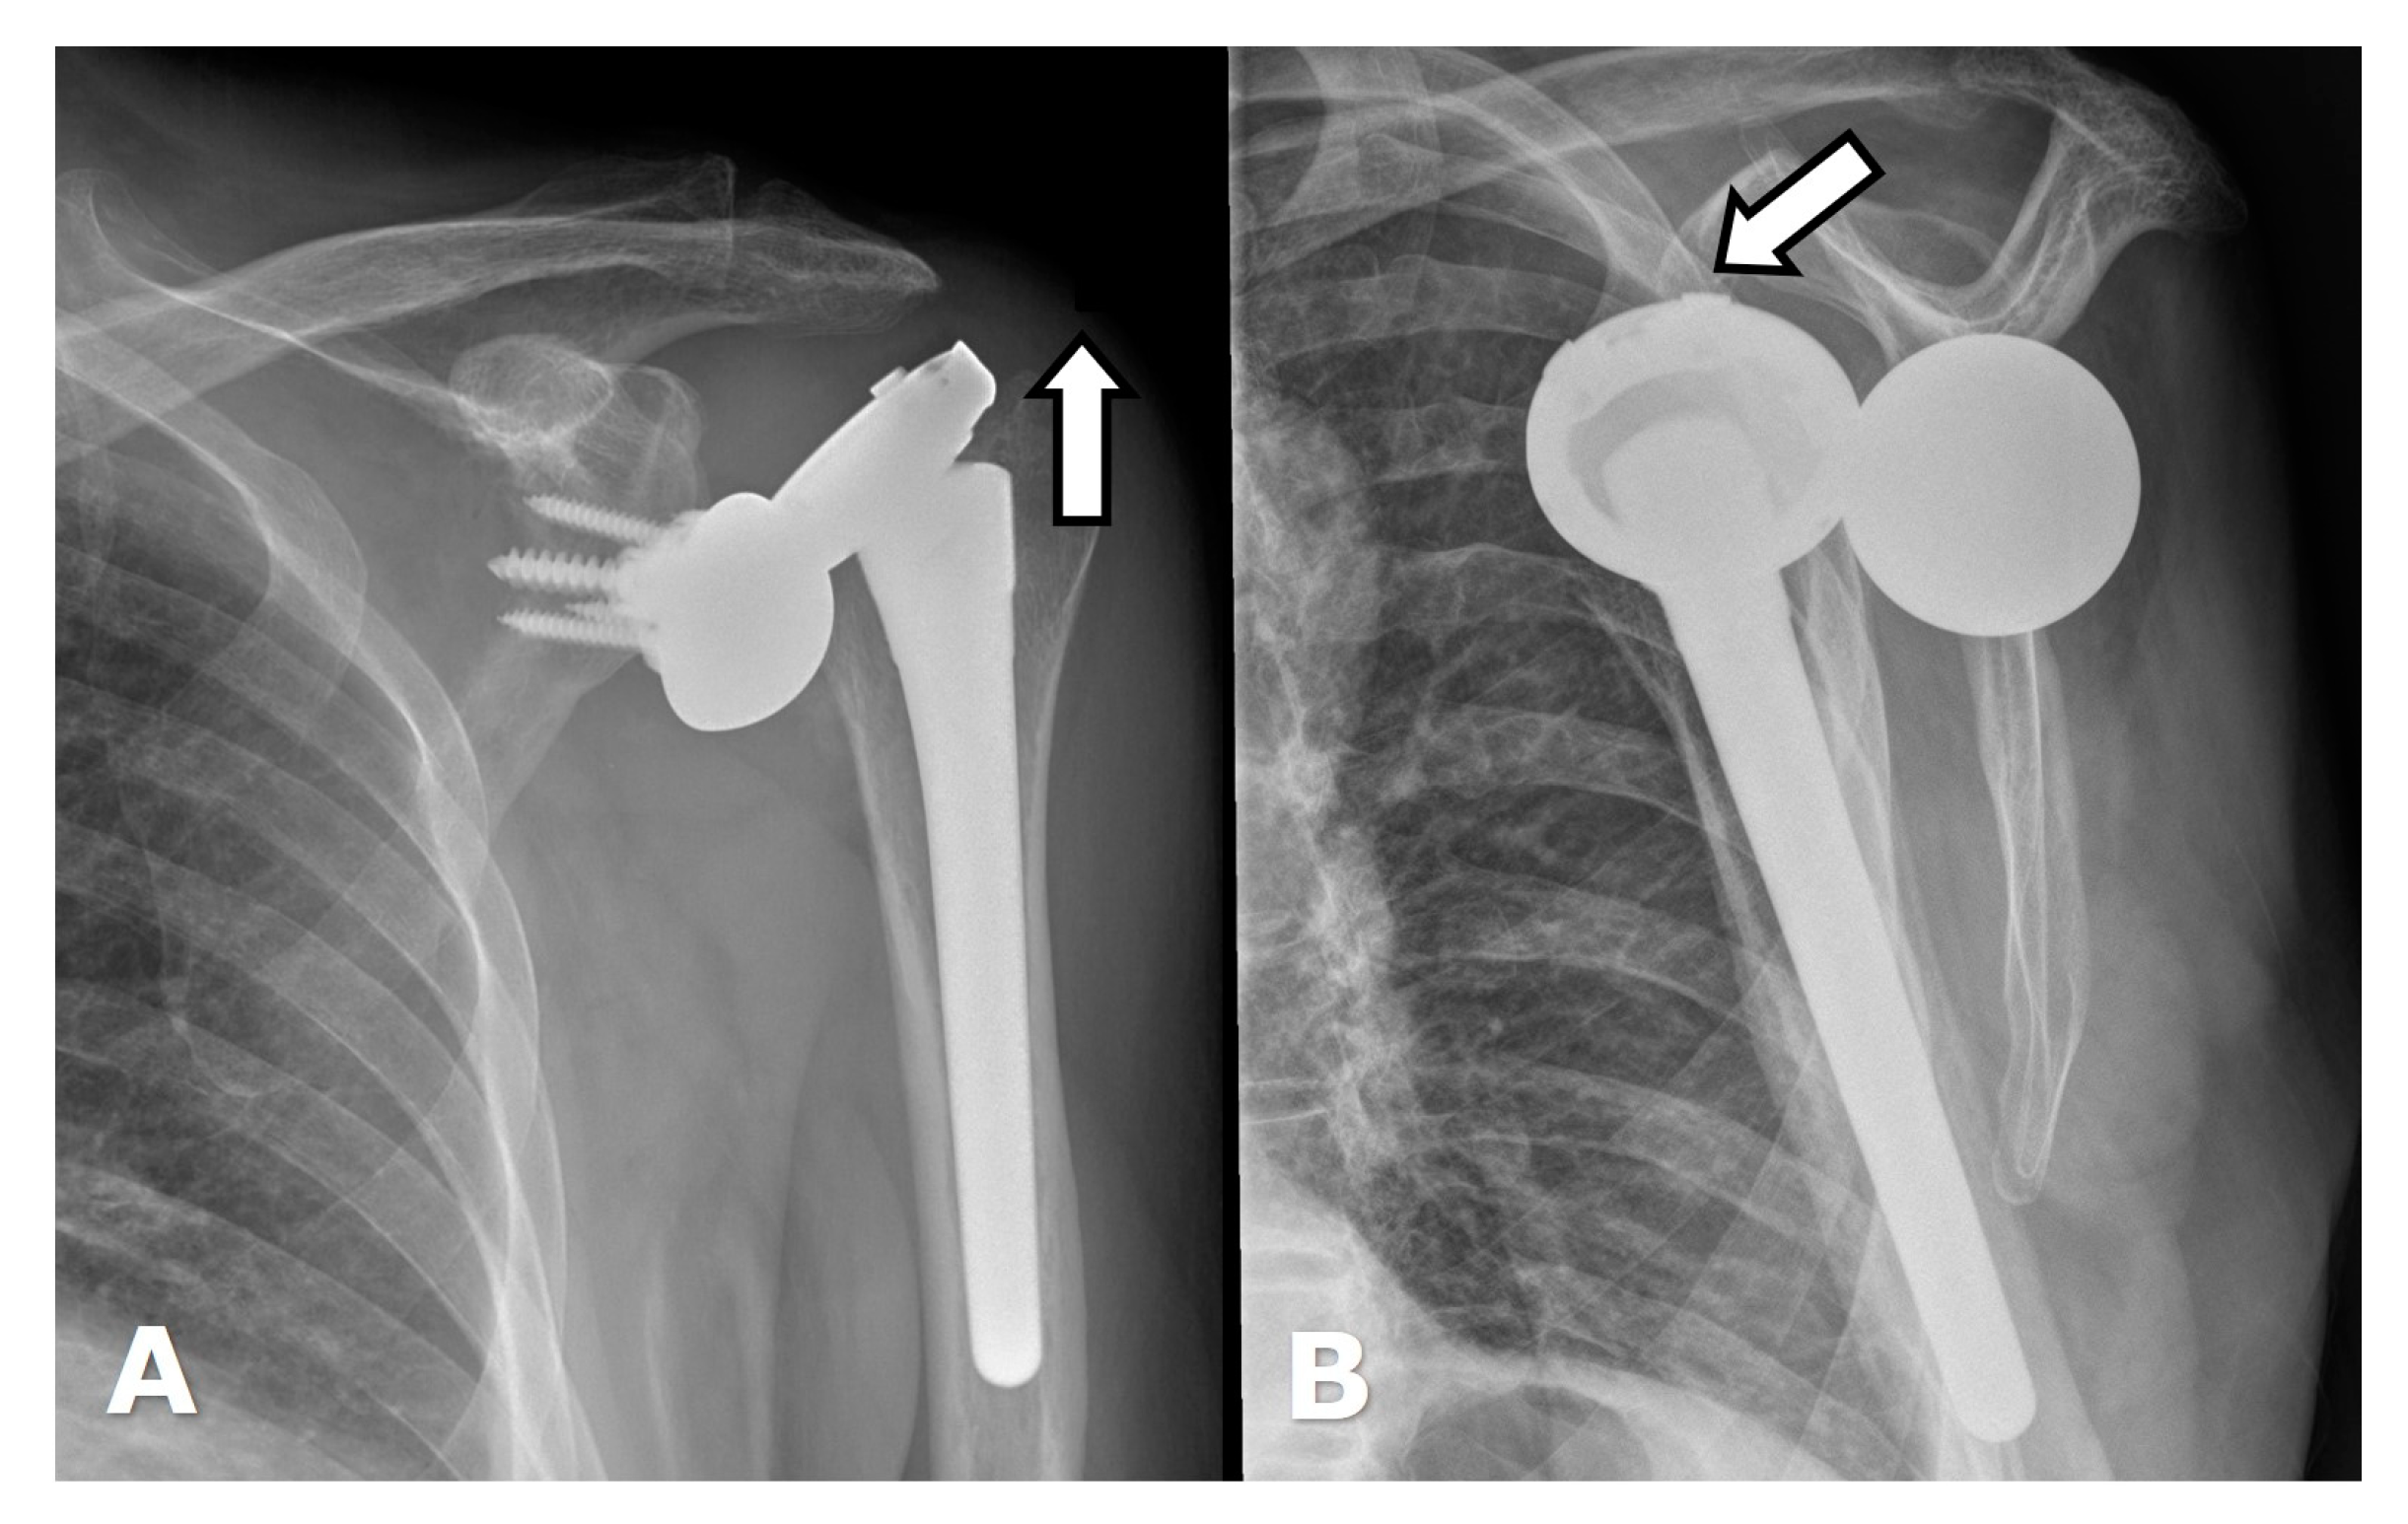

5.2. Reverse Arthroplasty

Reverse Total Shoulder Arthroplasty (RTSA)

4.3. Unique Complications